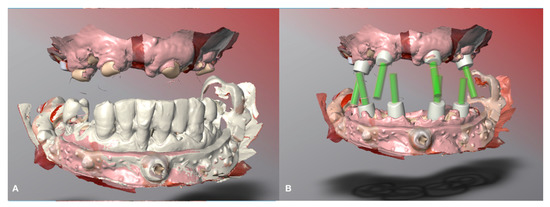

Digital lower preliminary impressions were taken (Figure 3) during the first visit using an intraoral scanner (Medit i500, Seoul, South Corea) and imported into CAD software (DWOS, Dental Wings Inc., Montreal, Canada, software version 3.7.0.26).

Figure 3. Preliminary digital impression. (A) Maxillary preliminary digital impression. (B) Mandibular preliminary digital impression.